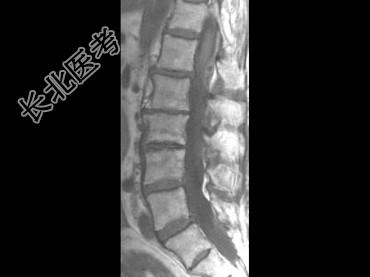

- 单项选择题男,59岁, 硬膜外麻醉后背痛1周余,结合MRI检查, 最可能的诊断是 ( )

E、硬膜外血肿